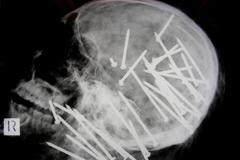

Canberra, Austrálie - Australská policie zveřejnila šokující rentgenový snímek.